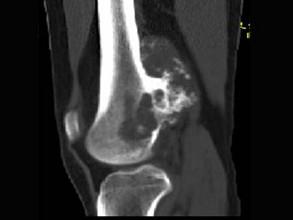

问题 女,20岁,右大腿远端疼痛2年,伴有肿块,请结合所提供图像,选择最佳答案 ( )

选项 A、纤维肉瘤 B、骨巨细胞瘤 C、软骨肉瘤 D、骨肉瘤 E、软骨黏液纤维瘤

答案 C